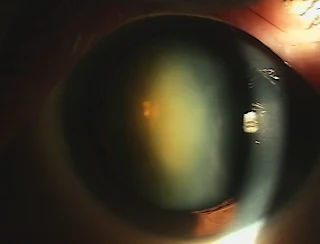

白內障:水晶體混濁造成視力不良

到目前為止醫學界仍無藥物可以治癒白內障。手術摘除混濁的水晶體及置入人工水晶體才是唯一有效的治療方式。白內障手術的時機一般依個人的生活需要而定,即視力障礙已經影響到日常工作與生活習慣時,就可以開刀了。隨著醫學的進步,眼科手術已進入顯微超音波手術的時代,人工水晶體的發展更是進入更高的境界(如:黃色非球面鏡片設計,或黃色多焦點繞射鏡片設計可看遠看近),使白內障手術後視力矯正更臻於完美,目前是以「小切口白內障超音波手術」加上「一體成型注射式人工水晶體」為手術方式,手術安全性高,手術時間短(約為15分鐘),傷口小(約3mm),不須打眼球後麻醉針,不須縫線(傷口自然癒合),不須住院,視力復原快,95%以上的病人具有手術後的最佳視力,術後大部份病人不需眼鏡,即可顯著改善視力,且均能相當滿意,並可提供穩定且長時間的清晰視力。通常病人在手術後只要遵守醫師指示及術後護理事項,2-3週後即與一般人無異。